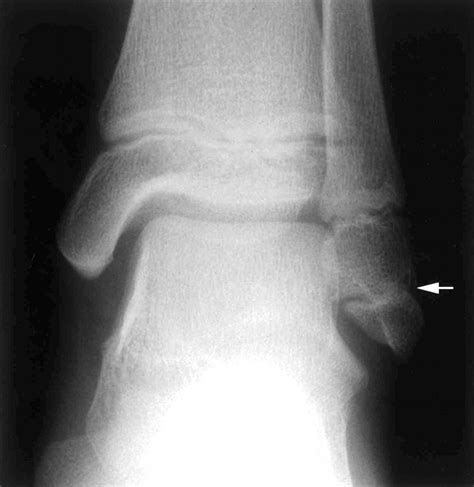

• X-Rays: X-rays are the primary imaging tool used to confirm the presence and extent of the fracture.

• CT Scans or MRIs: In some cases, more detailed imaging such as CT scans or MRIs may be required to assess the fracture and surrounding tissues.